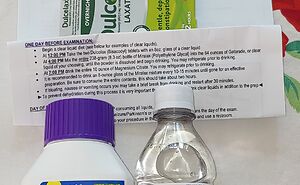

Challenge

Hey Pandas. Post A Picture Of Something You Saw Online And Absolutely Needed To Try At Home.